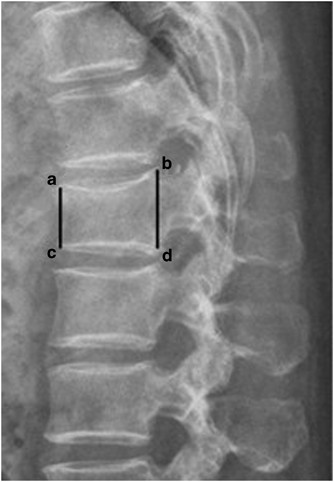

L1 Compression Fracture. Burst compression fracture of the l1 vertebral body is associated with a 35% loss of vertebral body height. Almost two years later, i was diagnosed with a chronic t9 compression fracture and multiple bulging i'm 29 years old. In very severe compression fractures, the back of the vertebral body may actually protrude into the spinal canal and put pressure on the spinal cord. Compression fractures of the spine usually occur at the bottom part of the thoracic spine (t11 and t12) and the first vertebra of the lumbar spine (l1). A compression fracture that occurs suddenly can be very painful, but a compression fracture that occurs gradually may cause pain only gradually. First, the fracture itself can cause significant pain, and media gallery. Distal radius fractures programme online course: There is a 3 mm retropulsion into the spinal canal, resulting in only mild canal. One and a half years back i got a compressed l1 fracture as a result of a car accident. The fracture line breaches both the anterior and posterior vertebral body cortex and the anterior superior endplate. Related online courses on physioplus. More often, the vertebra with a. The doctor suggested bracing for three. Lumbar compression fractures can be a devastating injury, therefore, for 2 reasons. Rarely, compression fractures occur in healthy vertebrae as a result of trauma.

Vertebral Compression Fractures Injuries Poisoning Merck Manuals Professional Edition. First, the fracture itself can cause significant pain, and media gallery. Compression fractures of the spine usually occur at the bottom part of the thoracic spine (t11 and t12) and the first vertebra of the lumbar spine (l1). There is a 3 mm retropulsion into the spinal canal, resulting in only mild canal. More often, the vertebra with a. Related online courses on physioplus. The fracture line breaches both the anterior and posterior vertebral body cortex and the anterior superior endplate. One and a half years back i got a compressed l1 fracture as a result of a car accident. The doctor suggested bracing for three. Lumbar compression fractures can be a devastating injury, therefore, for 2 reasons. Almost two years later, i was diagnosed with a chronic t9 compression fracture and multiple bulging i'm 29 years old. A compression fracture that occurs suddenly can be very painful, but a compression fracture that occurs gradually may cause pain only gradually. Burst compression fracture of the l1 vertebral body is associated with a 35% loss of vertebral body height. In very severe compression fractures, the back of the vertebral body may actually protrude into the spinal canal and put pressure on the spinal cord. Distal radius fractures programme online course: Rarely, compression fractures occur in healthy vertebrae as a result of trauma.

Over the weekend i have been experiencing pins and needles in my right hand and arm, a sensation of someone pouring cold water on my left thigh and. Sustained l1 compression fracture %20. They often occur in the upper lumbar segments as well, such as l1. What is it like to live with a compression fracture? More often, the vertebra with a. Related online courses on physioplus. I have lumber compression fracture and i want to know how much time i need to rest in bed, currently im having totally bedrest even my wife gives me food by her hand only i standup for toilet so im in very depression and also demotiveted please help me someone does it heal by itself? A t12 or l1 compression fracture most commonly happens as a wedge fracture, which occurs when the front part of the vertebra collapses compression fracture treatment options vary depending on the cause. In these situations, the fractures. I suffered a compression fracture to my spine (l2. Vertebral compression fractures (vcfs) occur when the bony block or vertebral body in the spine collapses, which can lead to severe pain, deformity and loss of height. Generally at your age unless you conservative : A compression fracture refers to a vertebral bone in the spine abrupting or collapsing as a result of pressure/degeneration of the spinal bones. Compression fractures of the spine usually occur at the bottom part of the thoracic spine (t11 and t12) and the first vertebra of the lumbar spine (l1). Patients who have one compression fracture are much more likely to compression fractures of the spine are common injuries, and often associated with conditions that weaken the bone. Vertebral compression fractures can be caused by a variety of reasons; Almost two years later, i was diagnosed with a chronic t9 compression fracture and multiple bulging i'm 29 years old. First, the fracture itself can cause significant pain, and media gallery. These compression fractures can occur in vertebrae anywhere in the spine, but they tend to occur most commonly in the upper back they rarely occur above the t7 level of the spine. Be careful not to load your spine. Fracture, slight scoliosis , bulging disc at l5/s1 and a schmorls node. The doctor suggested bracing for three. The fracture looks like more of a compression fracture than a burst fracture (there is no retropulsion of the l1 body posteriorly). Fluoroscopic view of a kyphoplasty procedure. The signs and symptoms of spinal compression fractures can come on gradually and vary from person to person. Nonsurgical options include activity restrictions, physical therapy, and treating osteoporosis. Compression fractures are the most common type of fracture affecting the spine. The fracture is stable and i am under the care of the physiotherapists. Vertebral compression fractures (vcfs) are the most common complication of osteoporosis, affecting more than 700,000 americans annually. In the lumbar region, where the most axial load is, the vertebrae of level l (1 and 2) are injured. Applying heat in the first few days after an injury draws more blood to the injury site, thus.